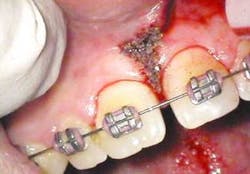

After infiltration of 1cc of local anesthetic solution, the Er:YAG laser (OpusDuo, OpusDent USA) was used at 350mj with a 1,000-micron, contact sapphire tip and heavy water spray to gently ablate the frenal attachment and underlying muscle tissue down to the level of the periosteum (figures 2, 3, and 4). Once this is accomplished, there is a small defect in the vestibular mucosa and interdental papilla where the frenal attachment and muscle once was. There is no charring, no burned tissue, and free bleeding in the site (figure 5).